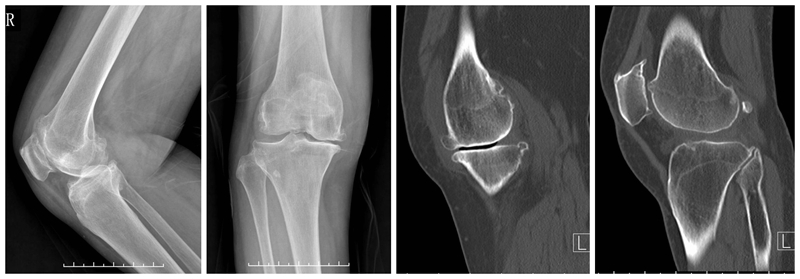

合并ACLD的单髁置换术

术前

术后检查

ACL损伤是否适合单髁置换,争议较大。需要鉴别原发韧带损伤继发OA还是原发OA继发ACL损伤。前者一般年龄轻,运动量大,适合一期或二期UKA联合ACL重建,后者一般年龄偏大,运动量少,需要术前详细评估膝关节稳定性。UKA仍是治疗内外不稳定的一种选择,而前后不稳定应探索其他治疗方案。髁间窝骨赘作为膝关节二级静态稳定结构。手术中引起撞击或磨损的骨赘要完全去除,其它骨赘建议保留。必须保留所有残留的ACL。适度减少胫骨后倾,一般应小于5°。